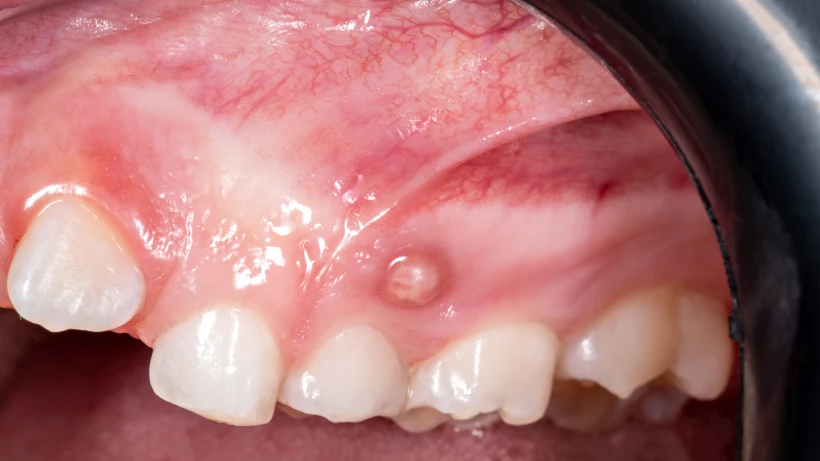

Свищ (синус-тракт) – это дренирующий канал, через который организм выводит гной из глубины тканей на поверхность слизистой (иногда даже на кожу лица). По сути, это «аварийный выход»: давление в очаге воспаления снижается, поэтому боль может уменьшиться или исчезнуть.

Свищ действительно может выглядеть как маленькая белая или желтоватая точка, иногда с выделениями. Но по природе это другое.

Как выглядит свищ на десне?Ответ на вопрос